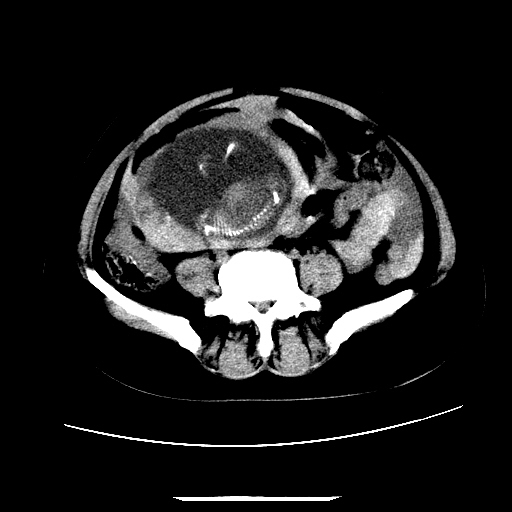

f,45y.怀孕4月晕倒,b超提示死胎,有手术结果,请展开讨论后明天告诉。

膈下-肠间隙内见气体密度影,子宫轮廓显示不清,宫腔-腹腔积液,首选考虑---子宫破裂出血。

1)宫腔妊娠。2)子宫破裂出血,腹腔及盆腔积血。

感谢同行们的高见。手术结果:子宫破裂出血。

我们的诊断是:腹、盆腔积液(考虑腹盆腔脏器破裂出血);宫腔妊娠。让人纳闷的是当时我们没有经验,现在回头看看分析:4月宫腔妊娠:1、洋膜囊不可能紧贴胎体这么小;2仔细看看子宫后壁肌层模糊不清;3腹、盆腔液体来源原因?4、45岁高龄妊娠有晕倒。由此可大胆诊断:宫腔妊娠子宫破裂出血。